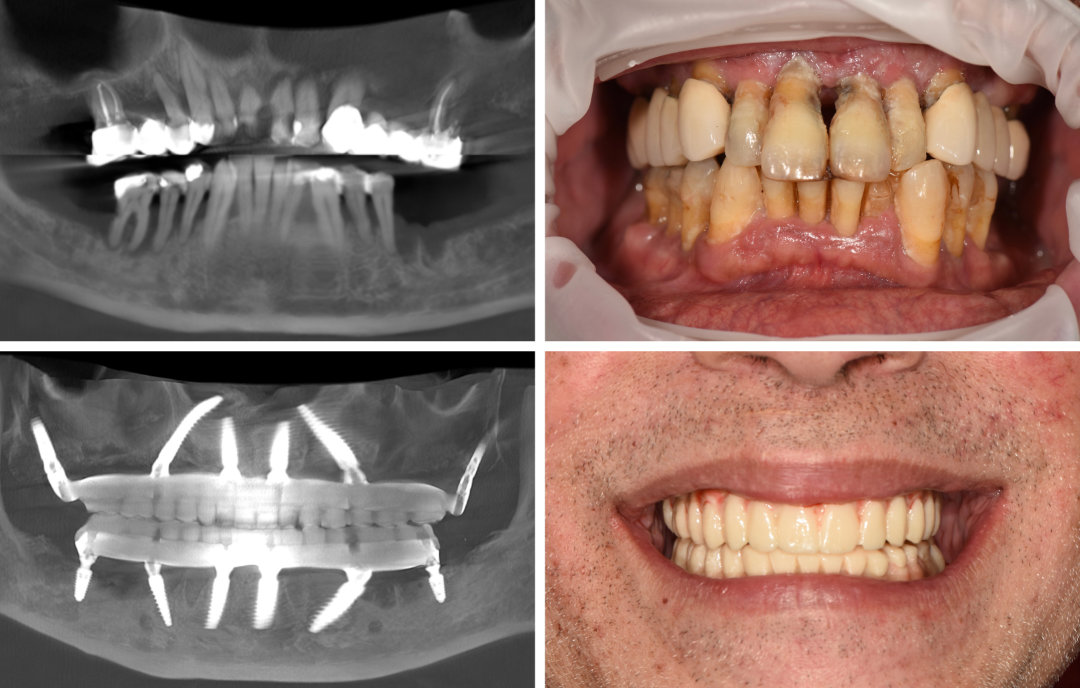

Ausgangssituation

Ein 55-jähriger Patient aus dem Ausland stellte sich mit generalisierter Parodontitis vor. Die Zähne waren sehr locker. Wir entschieden uns zusammen für eine Extraktion der Zähne und eine implantologische Gesamtrehabilitation beider Kiefer.

Lösung

In Ober- und Unterkiefer wurden jeweils sechs Implantate nach digitaler Planung mittels dynamischer Navigation inseriert. Da der Patient aus dem Ausland kam, erfolgte die komplette Behandlung innerhalb von neun Arbeitstagen. Am OP-Tag erhielt er eine festsitzende Sofortversorgung, anschließend eine provisorische, mit Titansteg verstärkte Brücke. Nach 4 Monaten erhielt der Patient definitive Brücken im Ober- und Unterkiefer.

Vorteile

Trotz der schweren Ausgangslage konnte der Patient in kurzer Zeit funktionell und ästhetisch rehabilitiert werden. Der Fall zeigt die Effizienz und Planbarkeit moderner navigationsgestützter Implantologie, daher eignet sich unser Konzept insbesondere für Patienten , die aus dem Ausland zu uns kommen.